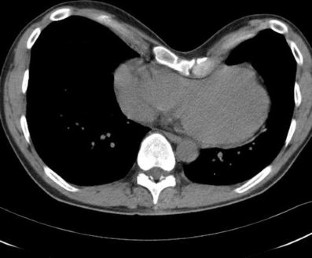

Cardiological screening included medical history taking, physical examination, electrocardiography, transthoracic echocardiography and treadmill cardiography. Complaints, symptoms and test results were arranged in a clinical score. Indication for a therapeutic surgical correction by a modified Ravitch operation was a high clinical score in combination with radiological evidence of cardiac compression on CT or MRI.

Fig. 1

Fig. 2

Fig. 3

Fig. 4